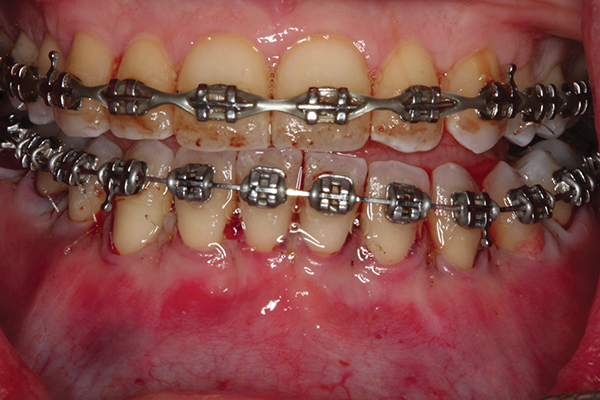

Fig 1. Preoperative SFOT. No loss of attachment, but thin dentoalveolar bone phenotype noted clinically.

Figure 1